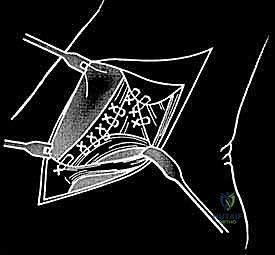

* الإصلاح المباشر (Direct Repair): إذا كانت أنسجة الرباط الممزقة ذات جودة جيدة (عادة في الإصابات الحديثة)، يقوم الدكتور هطيف بخياطتها مباشرة. يستخدم خطاطيف تثبيت عظمية (Suture Anchors) صغيرة جداً ومصنوعة من مواد متوافقة حيوياً (تذوب مع الوقت أو من التيتانيوم) لغرس الخيوط القوية في عظمة الكعب الإنسي، ثم يتم سحب الرباط الممزق وتثبيته بقوة في مكانه التشريحي الأصلي.

- إعادة البناء (Reconstruction): في الحالات المزمنة حيث يكون الرباط الأصلي قد تليف، تآكل، أو أصبح غير كافٍ للاستخدام، يلجأ الدكتور هطيف إلى تقنية "إعادة البناء". تتضمن هذه التقنية المتقدمة استخدام رقعة وترية (Graft)، إما من جسم المريض نفسه (Autograft - مثل أوتار الركبة أو وتر من القدم) أو رقعة صناعية متطورة. يتم حفر أنفاق ع